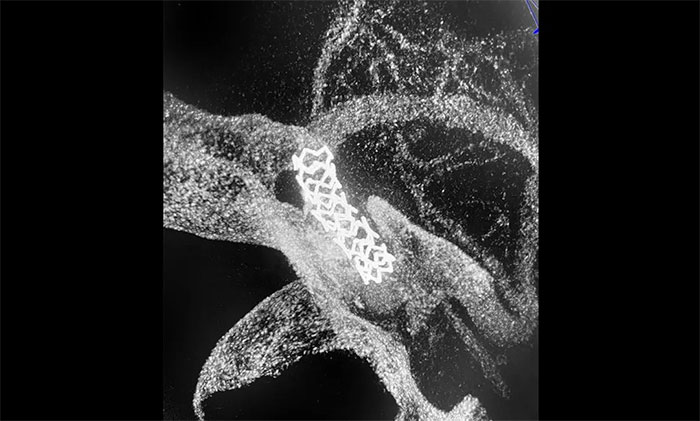

随后,微导丝超选至左侧大脑中动脉M1段远端,并以多枚球囊扩张残余重度狭窄处,造影提示狭窄较前明显改善,远端血流改善明显。最后顺利放入支架,造影提示支架贴壁良好,支架内血流通畅,远端血流良好,手术顺利完成。